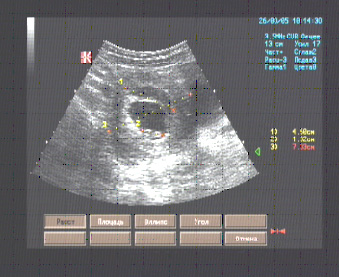

Эхографические признаки ретрохориальной гематомы при маточной беременности сроком 8 недель. Протокол УЗИ

Матка 104 х 88 х 73 мм., anteflexio, шаровидной формы, типичного расположения, контуры ровные, миометрий изоэхогенный, в полости плодный пузырь диаметром 42 мм. с одним эмбрионом – КТР 17 мм., пульсация сердечной трубки которого отчётлива; в миометрии вдоль левой боковой стенки и верхушки плодного пузыря анэхогенный серповидной формы участок размерами 40 х 14 мм.; на остальном протяжении миометрий однородный.

Эхографические признаки ретрохориальной гематомы при маточной беременности сроком 8 недель.